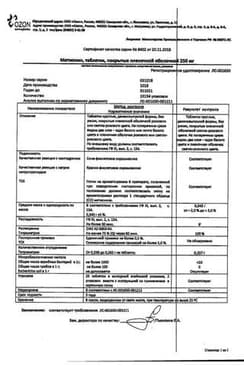

Метионин таблетки покрытые оболочкой упаковка контурная ячейковая 250 мг 50 шт

Инструкция по применению Метионин таблетки 250 мг 50 шт

Общие характеристики

Состав препарата Метионин

Таблетки, покрытые оболочкой розового цвета, круглые, двояковыпуклые; на поперечном разрезе видны два слоя.

1 таб.

метионин 250 мг

Вспомогательные вещества: крахмал картофельный, кремния диоксид коллоидный, кальция стеарат, полисорбат 80, сахароза, патока крахмальная, мука пшеничная, азорубин (краситель кислотный красный), воск пчелиный, масло подсолнечника.

10 шт. - упаковки ячейковые контурные (5) - пачки картонные.